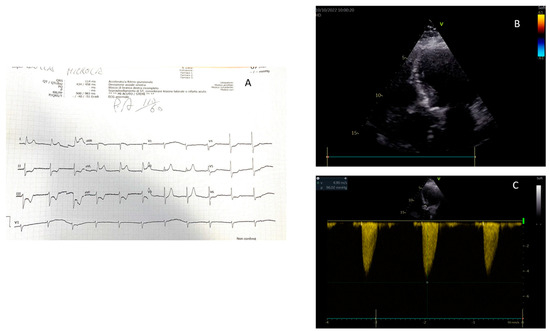

| Papillary muscle rupture and acute mitral regurgitation |

| Ventricular septal defect |

| Rupture of the ventricular free wall |

| Pseudoaneurysm |

| Left ventricular apex thrombosis |